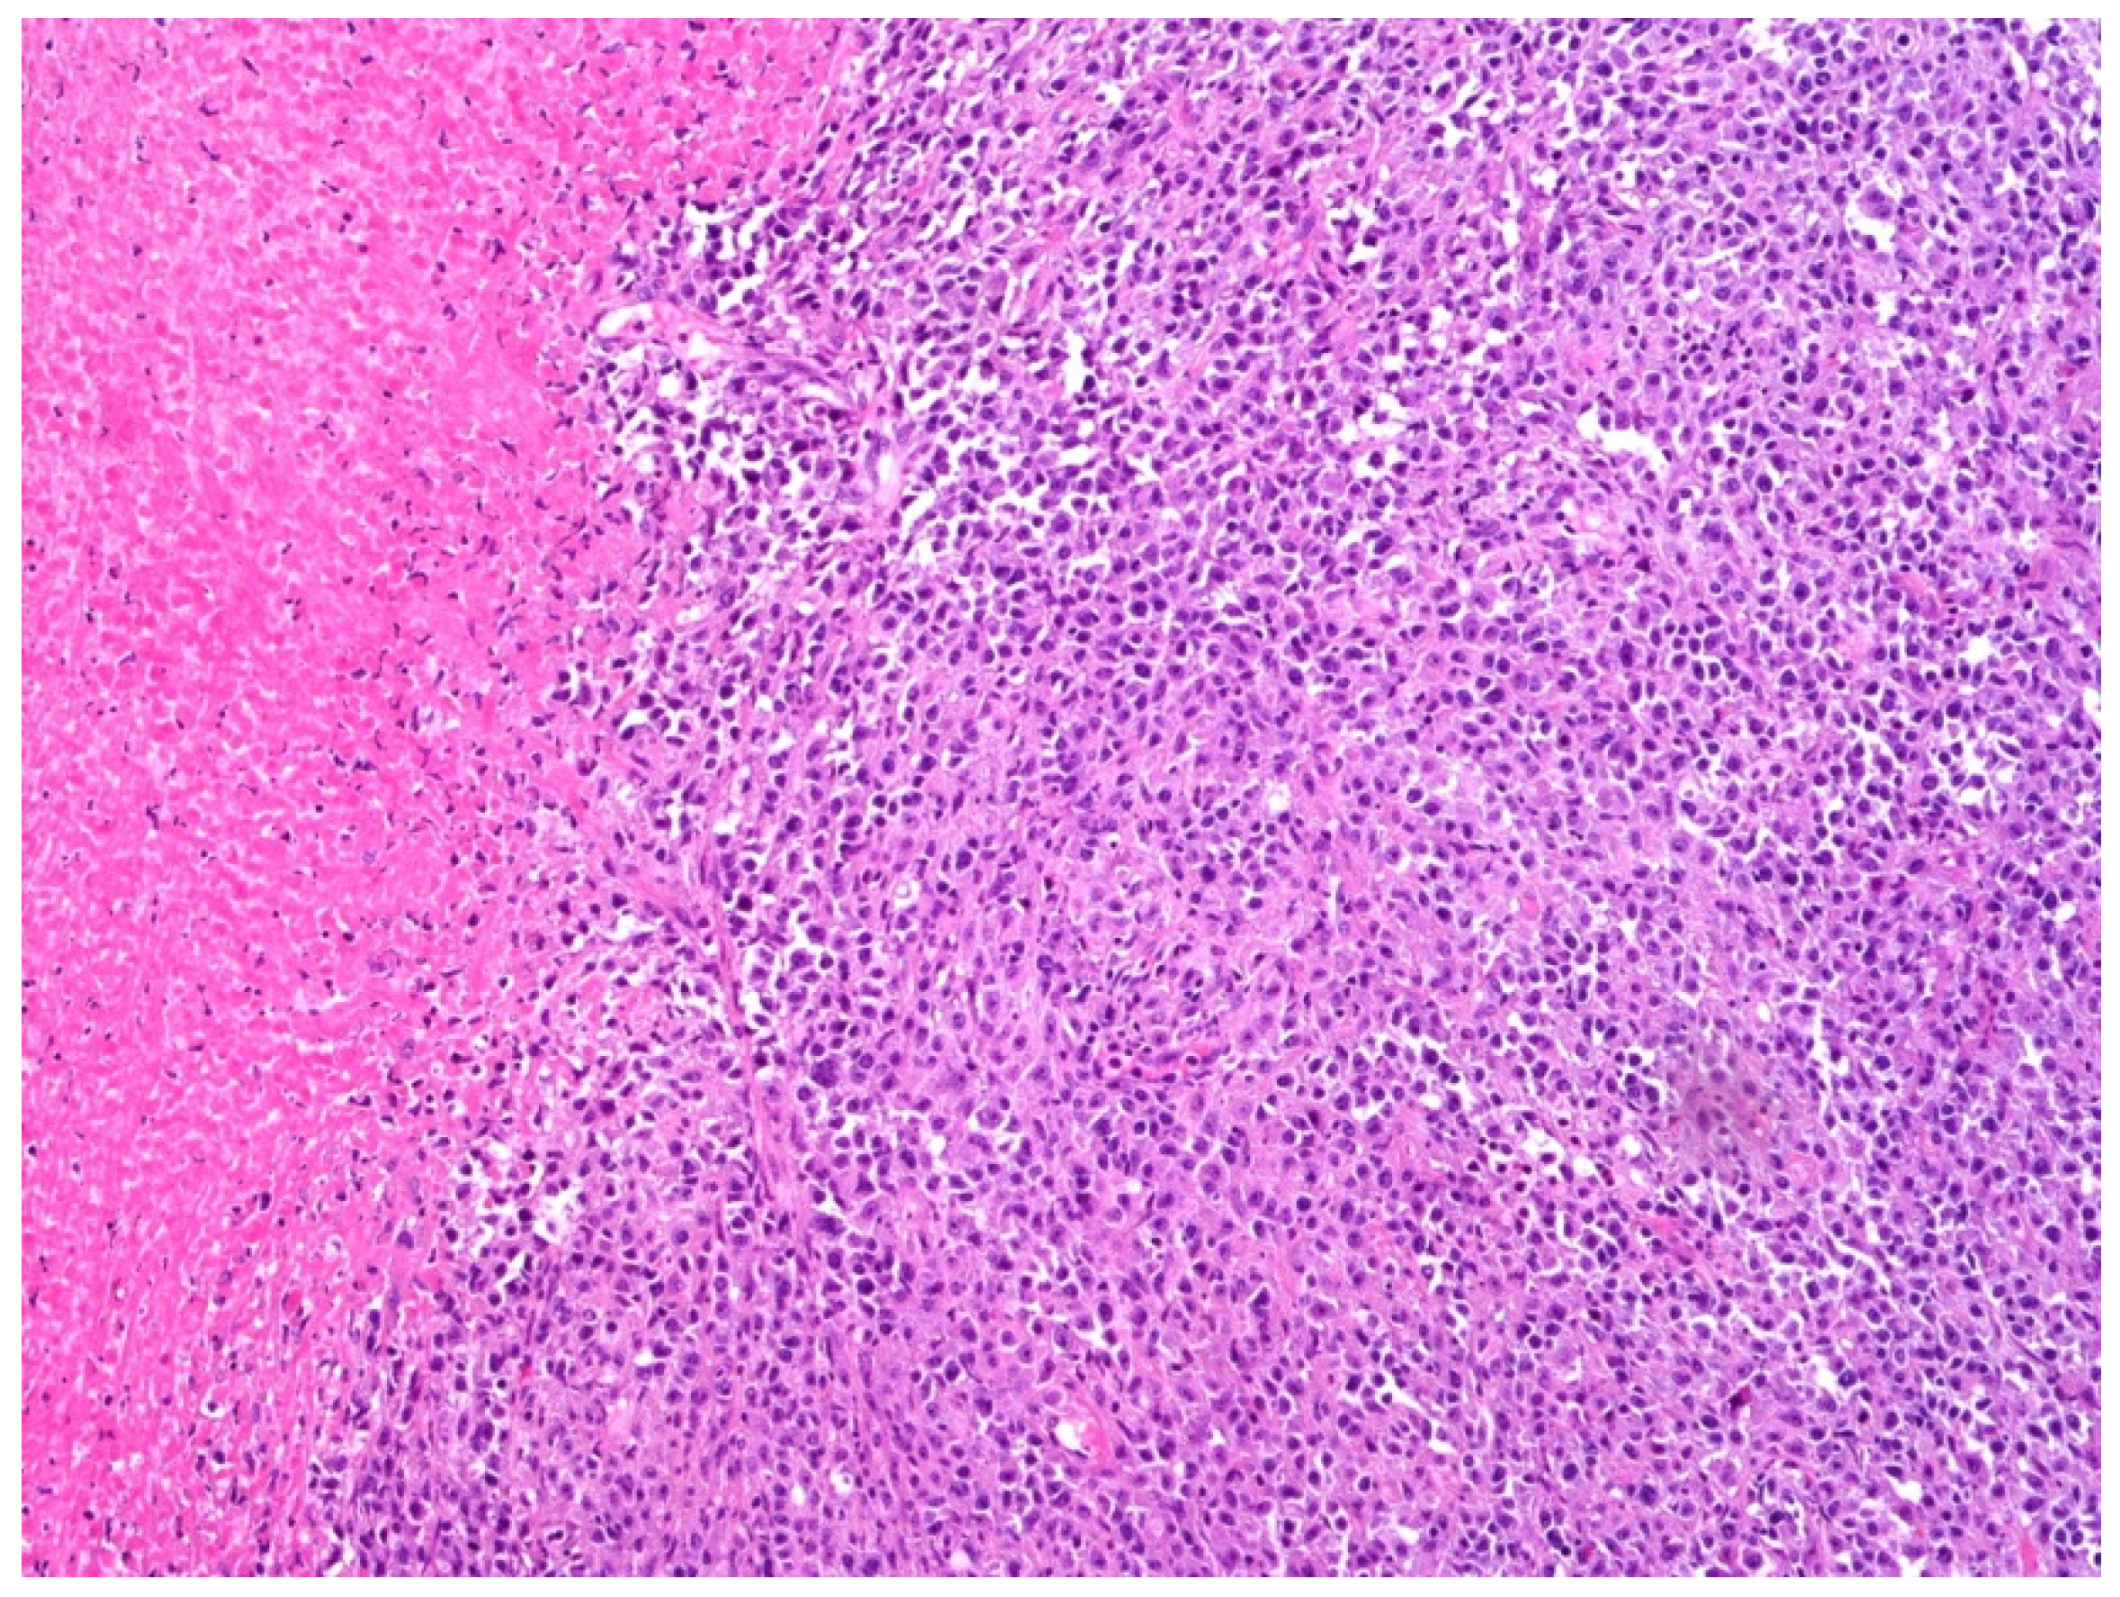

5. Histology, Immunophenotype, and Genetic Features of DLBCL, NOS

6. EBV-Positive DLBCL, NOS and Primary Bladder Lymphoma

7. Differential Diagnoses and Potential Diagnostic Pitfalls